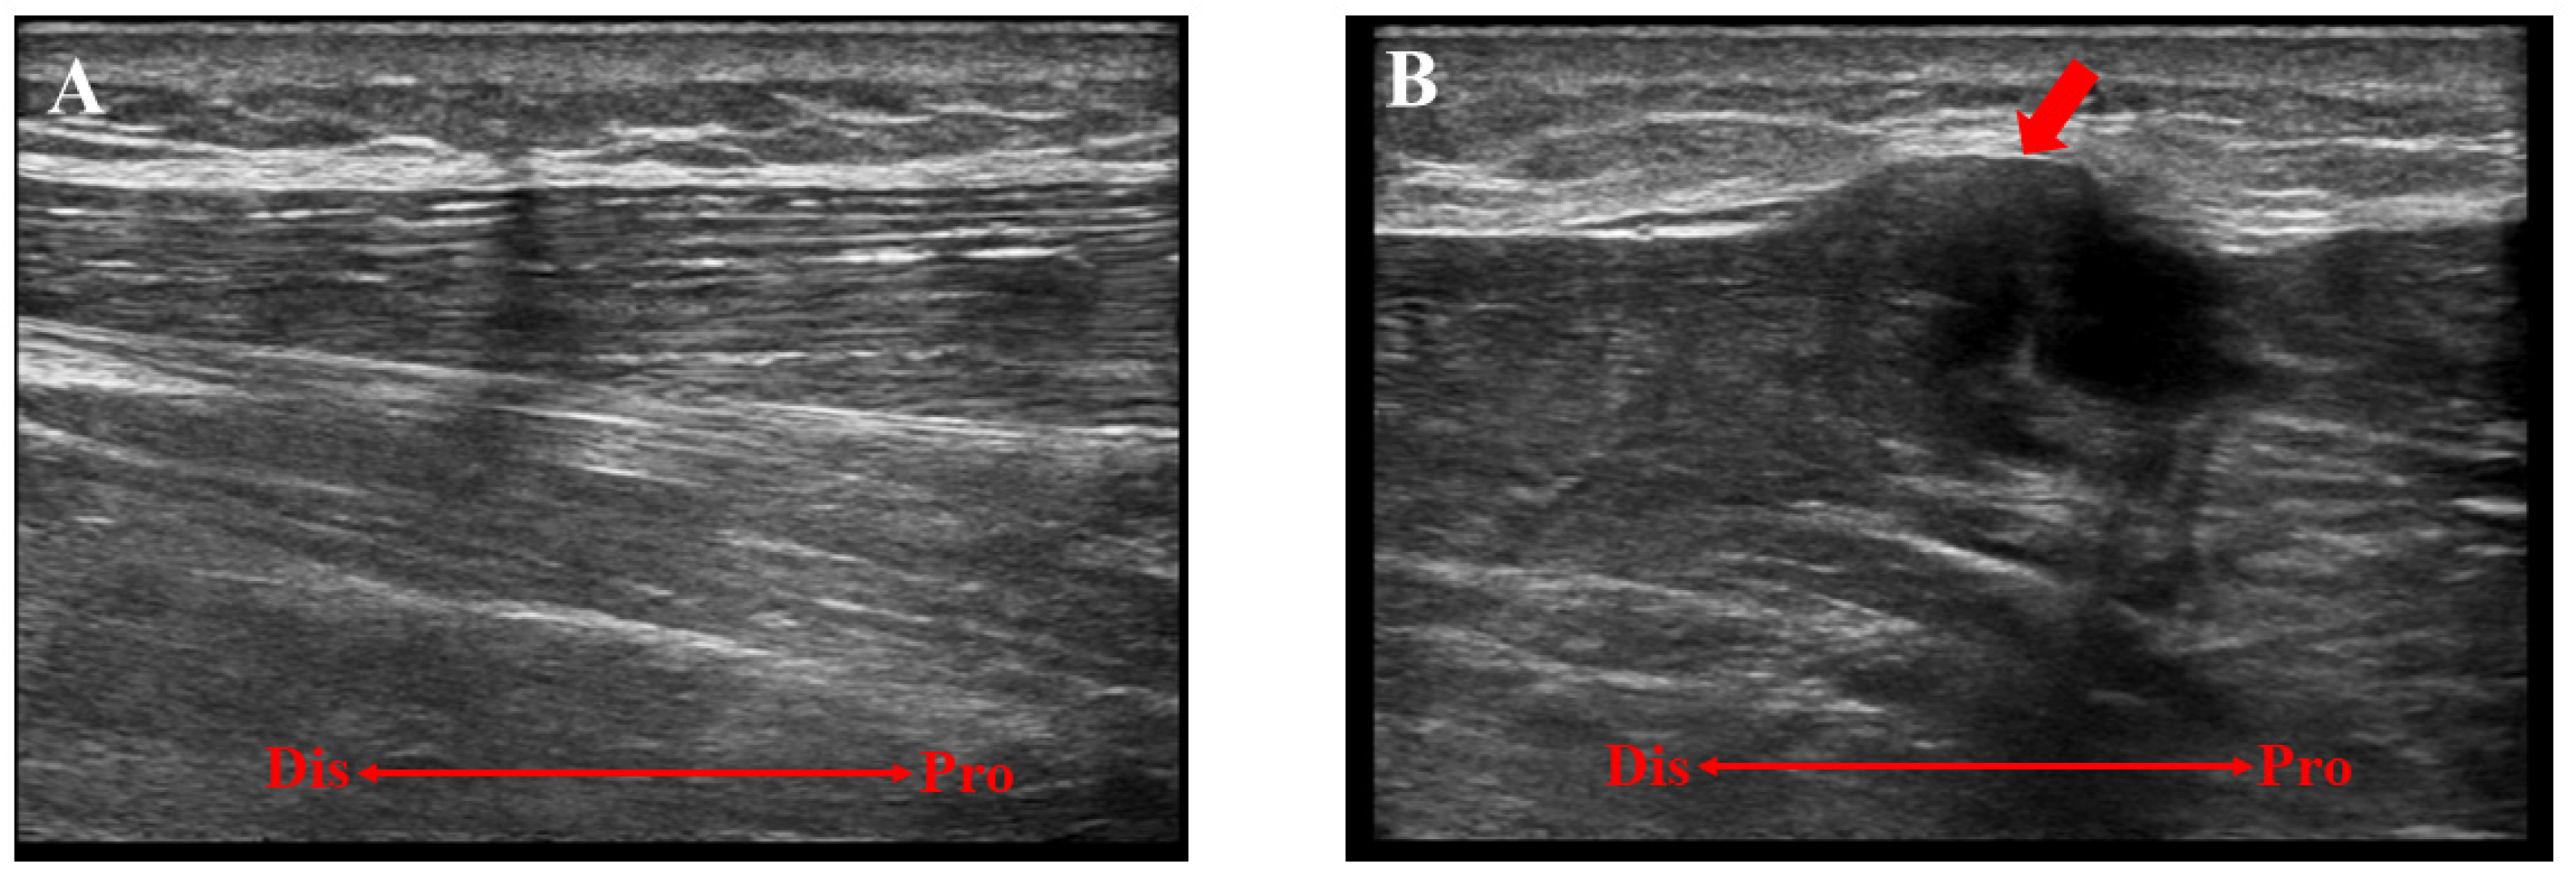

Postoperatively, the ankles were not immobilized, and weight bearing was allowed as tolerated. Ankle range-of-motion exercises were initiated immediately after surgery. Several days after surgery, he presented with paresthesia and impaired touch sensation over the dorsal area of the left foot. At the three-month follow-up, a swelling lesion with hard elasticity was identified between the middle and the most distal surgical wounds. The lesion did not disappear with the patient in the supine position. On palpating this lesion, he recognized a radiating sensation over the left dorsal foot supplied by the SPN. An ultrasonographic examination showed an isolated lesion (8.0 × 12.0 mm) (Figure 5). MRI showed a lesion that was iso-signal on T1-weighted images and high signal on T2-weighted images (Figure 6). Traumatic neuroma of the SPN was considered. While the lesion did not disappear, he returned to playing baseball six months after surgery. At the 24-month follow-up examination, recurrent TAMHs were not found in the bilateral lower extremities. The patient was asymptomatic without palpation of the lesion and did not demand surgical intervention for this lesion.

Figure 5. The ultrasonographic findings of the traumatic neuroma of the superficial peroneal nerve (12 × 8 mm) (red arrow). (A) A long-axis view. (B) A short-axis view. Dis, distal; Pro, proximal; M, medial; L, lateral.